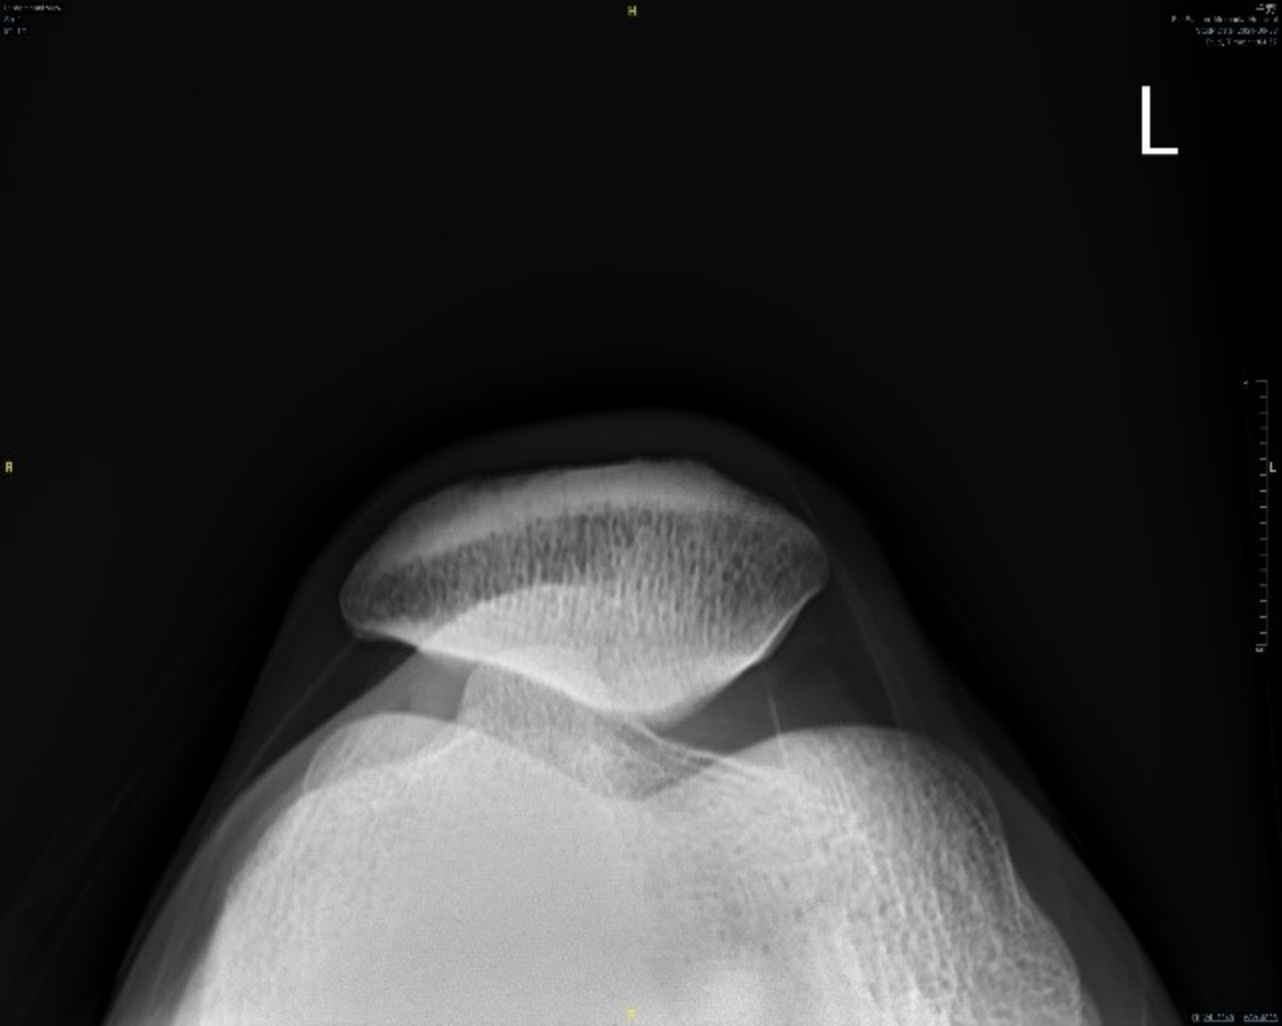

髕骨股骨疼痛症候群的患者常會有跑步時覺得膝蓋內外側的疼痛,或是蹲下站起時膝蓋卡卡或疼痛、膝關節僵硬腫脹、膝蓋彎曲時常有喀啦聲響。針對髕骨股骨疼痛症候群的檢查及診斷,可以藉由病史及理學檢查評估疼痛及受損部位,必要時並配合X光檢查髕骨外翻的程度(圖一)、超音波檢查內外髕支持帶有無受損(圖二)、核磁共振檢查髕骨下的軟骨有無受損情形。